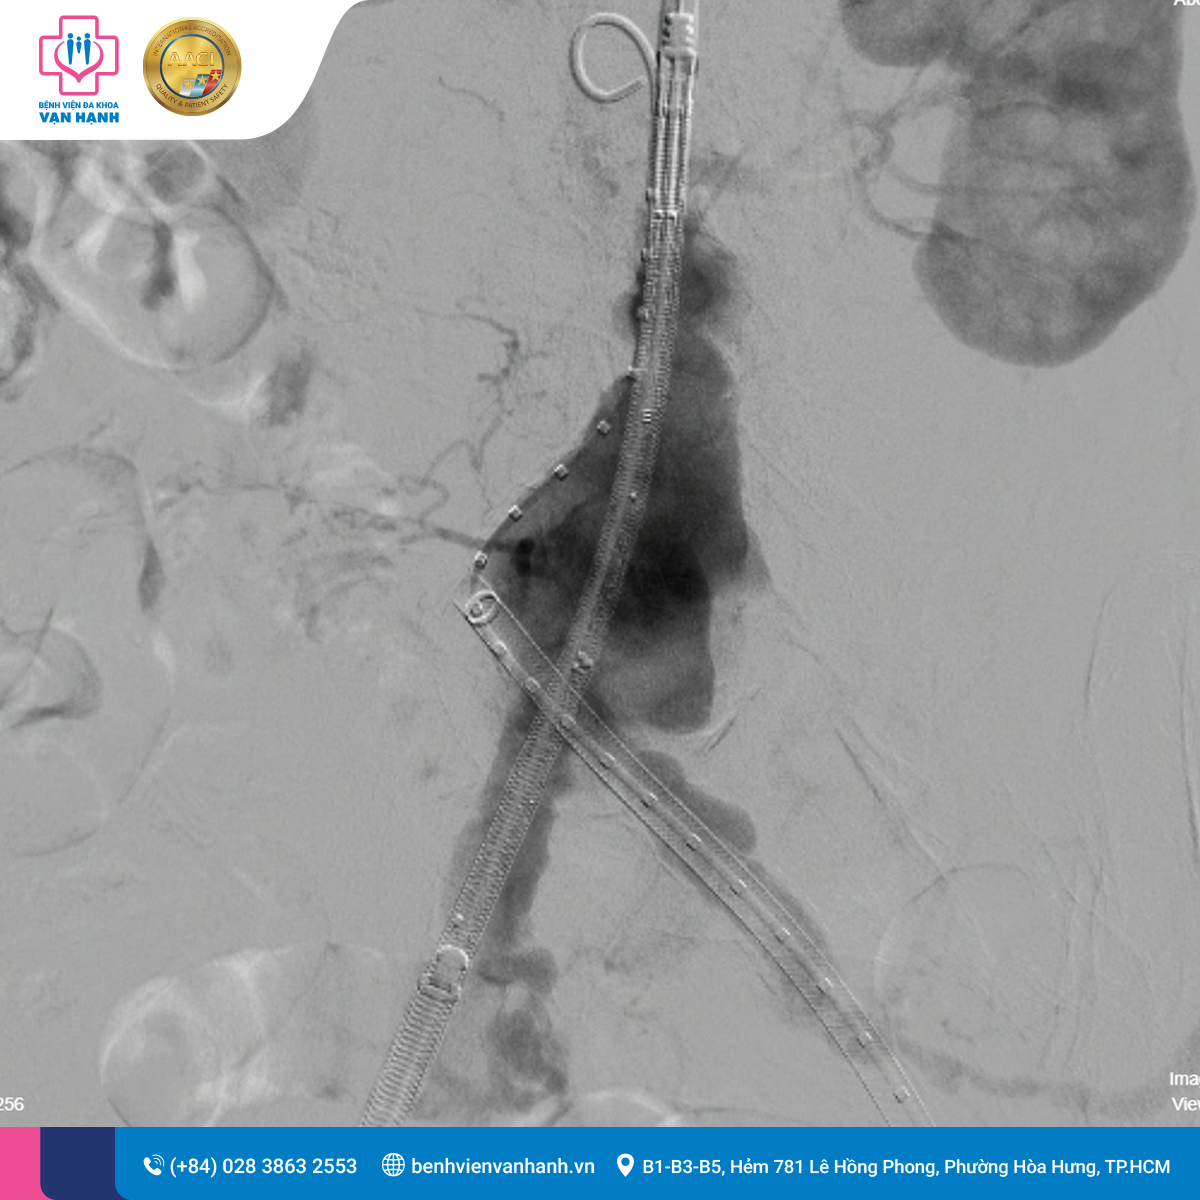

Sau khi hội chẩn, ekip bác sĩ quyết định thực hiện phương pháp Đặt Stent Graft động mạch chủ bụng dưới hướng dẫn của máy chụp mạch số hóa xóa nền (DSA).

Quá trình: Các bác sĩ đưa dụng cụ qua một lỗ châm nhỏ ở động mạch đùi, luồn Stent Graft lên vị trí túi phình để tạo ra một lòng mạch mới bền vững, loại bỏ áp lực máu lên thành túi phình.

Kết quả: Cuộc phẫu thuật diễn ra thuận lợi trong 1,5 giờ. Bệnh nhân hồi phục ngay sau mổ, các chỉ số sinh hiệu ổn định. Sau 3 ngày theo dõi tại Bệnh viện Đa khoa Vạn Hạnh, bệnh nhân đã được xuất viện trong tình trạng sức khỏe ổn định.